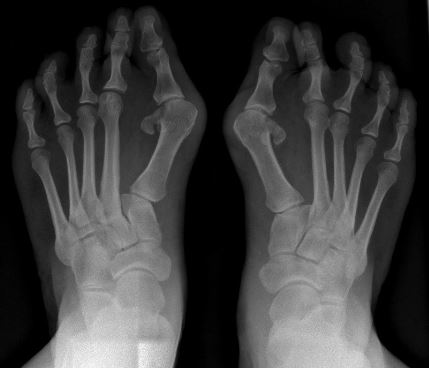

Radiographies d’hallux valgus